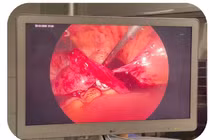

Đây là trường hợp hiếm gặp và xử trí rất khó khăn bởi người bệnh có 2 thai, 1 thai bên ngoài vỡ, thai bên trong phát triển tốt. Thai ngoài tử cung thường gây ra nhiều biến chứng nguy hiểm.

Bệnh viện Phụ Sản Hà Nội đã cấp cứu thành công cho một bệnh nhân bị chửa ngoài tử cung vỡ, chảy máu ồ ạt trong ổ bụng dẫn đến tình trạng choáng váng. Phát hiện sớm giúp cứu sống sản phụ và bảo tồn khả năng sinh sản.